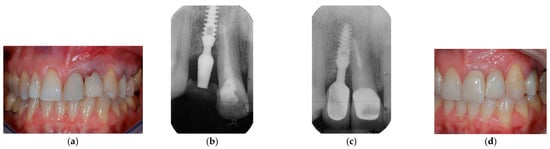

2.9. Clinical Cases and Study Diagram

- Lombardo, G.; Corrocher, G.; Pighi, J.; Mascellaro, A.; Marincola, M.; Nocini, P.F. Esthetic Outcomes of Immediately Loaded Locking Taper Implants in the Anterior Maxilla: A Case Series Study. J. Oral Implantol. 2016, 42, 258–264. [Google Scholar] [CrossRef]